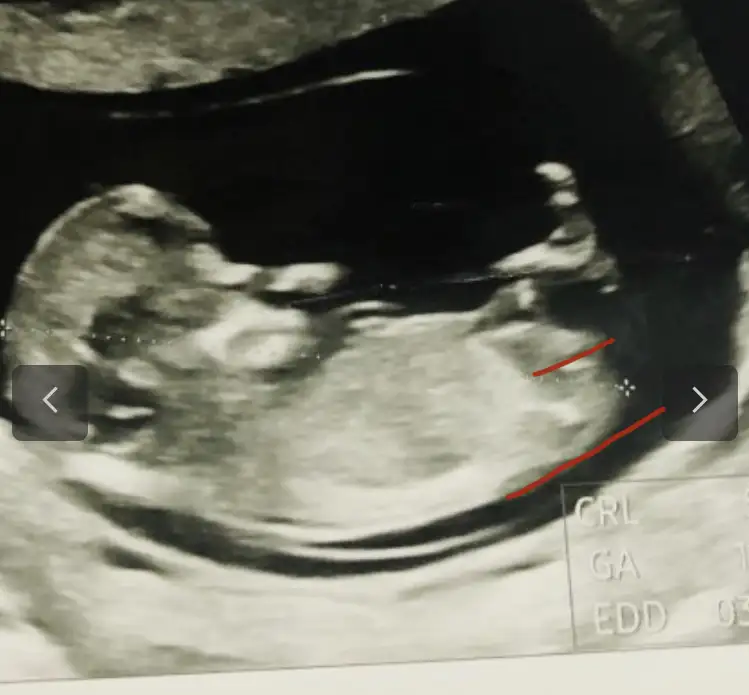

Belli belirsiz tam o bölge ama sanki kız gibi canım. Eki Görüntüle 2957287

Kafası dışında hiçbir şeyi ayırt edemiyorum. Yamuk yumuk bir şekil görüyorum sadece.